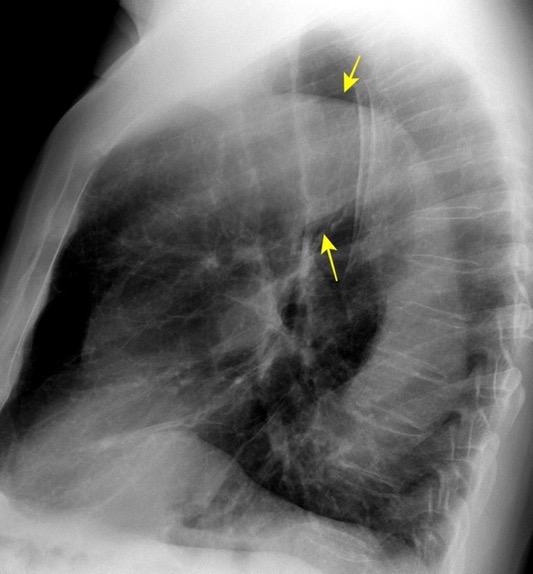

Visible: 88%

Depresión ligera…….55% profunda. 35%

FRECUENTES Ganglios. (más frecuente)

Webb R. 2005 Aneurisma aórtico Disección aórtica con aneurisma Masa mediastínica (incl. Ca. de pulmón)

Boiselle PM et-al. Imaging of mediastinal lymph nodes: CT, MR, and FDG PET. Radiographics. 1998